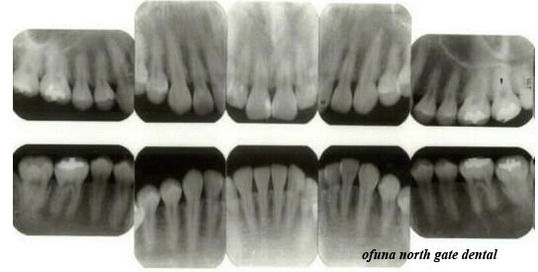

下の写真は、骨吸収がまったくない健康な状態のレントゲン写真です。

下の写真は、骨吸収が2/3以上ある重度歯周病のレントゲン写真です。

歯周病になると骨吸収が大きくなってくるのが分かるかと思います。

前置きはこれくらいにして早速 初診時のレントゲンを見てみましょう。

以下が初診時です。